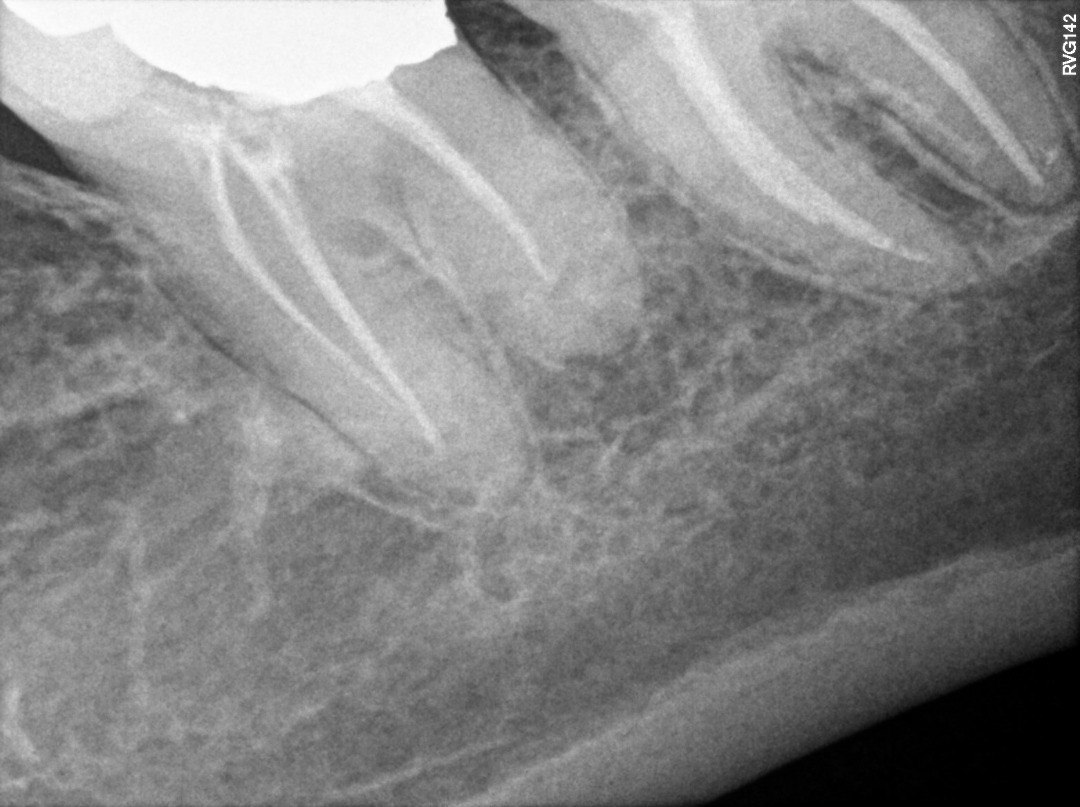

5. What option can be selected for root canal treatment of tooth # 1.5?

6. What option can be selected for root canal treatment of tooth # 1.4?

7. What condition can be selected or the root canal treatment of tooth # 4.6?

8. What condition can be selected or the root canal treatment of tooth # 3.6?